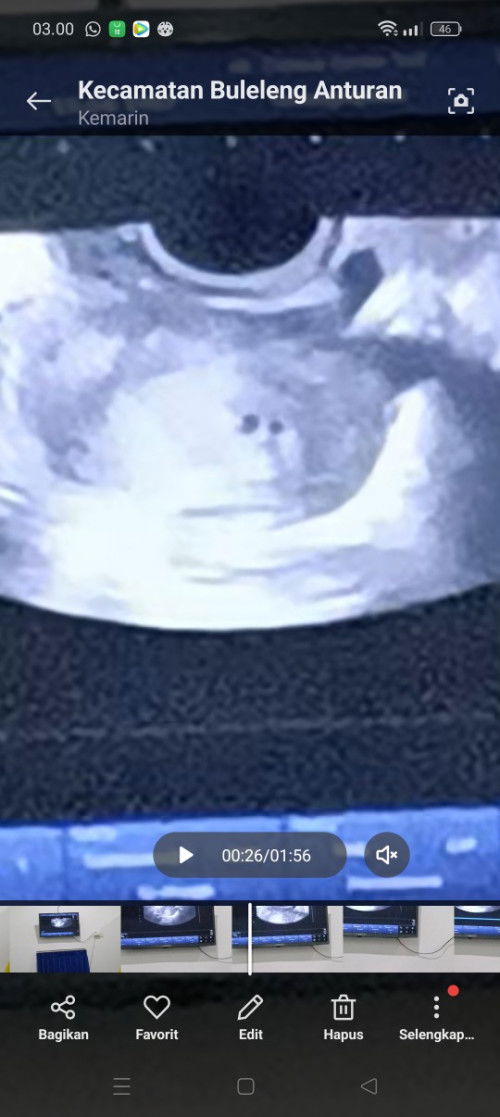

Salah liat apa memang ada 2 kantong janin

Apa saya salah lihat atau gmna ni Bun... Saya liat seperti 2 kantong kehamilan Pas di USG dokter nya pun dr nya gak notis klok itu 2 Bener 2 atau 1 ya Bun Semoga aja kembar 🤲 Baru ngeh pas saya liat vidio USG nya